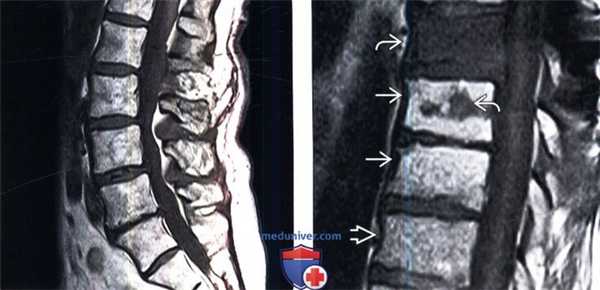

(Слева) Сагиттальный срез, Т2-ВИ, 15-летний пациент: жировая перестройка костного мозга, ограниченная зоной вокруг центральных дренирующих вен каждого позвонка. Остальная часть тел позвонков заполнена красным костным мозгом. Подобная МР-картина типична для пациентов молодого возраста.

(Справа) На сагиттальном Т1-ВИ 50-летнего пациента определяется смешанная картина «ткани в горошек», характеризующаяся перемежающимися друг с другом участками красного и желтого костного мозга. Жировой костный мозг обычно локализуется вокруг дренирующих вен и вблизи замыкательных пластинок. Красный костный мозг характеризуется аналогичной или несколько повышенной по сравнению с мышцами интенсивностью сигнала.

(Слева) На сагиттальном Т1-ВИ 85-летнего пациента определяется практически полная жировая перестройка костного мозга тел позвонков, на фоне которой видны лишь небольшие фокусы эритропоэтического костного мозга. Красный мозг с возрастом подвергается инволюции, однако небольшие его очаги в позвонках, если пациент ранее не получал лучевую терапию, сохраняются всегда.

(Справа) Сагиттальный срез, Т1-ВИ: выраженная разница в интенсивности сигнала между нормальным желтым костным мозгом, изменениями костного мозга на фоне лучевой терапии и опухолевой инфильтрацией костного мозга.

(Справа) На сагиттальном Т1-ВИ 50-летнего пациента определяется смешанная картина «ткани в горошек», характеризующаяся перемежающимися друг с другом участками красного и желтого костного мозга. Жировой костный мозг обычно локализуется вокруг дренирующих вен и вблизи замыкательных пластинок. Красный костный мозг характеризуется аналогичной или несколько повышенной по сравнению с мышцами интенсивностью сигнала. (Слева) На сагиттальном Т1-ВИ 85-летнего пациента определяется практически полная жировая перестройка костного мозга тел позвонков, на фоне которой видны лишь небольшие фокусы эритропоэтического костного мозга. Красный мозг с возрастом подвергается инволюции, однако небольшие его очаги в позвонках, если пациент ранее не получал лучевую терапию, сохраняются всегда.